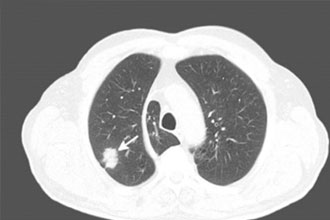

侵袭性真菌病肺部影像学表现(真菌感染区呈现团块状高密度阴影)

(图片来源:veer图库)